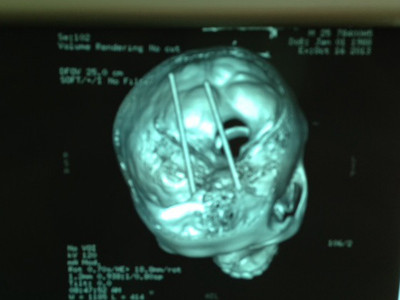

Đôi đũa đâm xuyên sọ được chụp lại qua CT Scan

Đôi đũa đâm xuyên sọ được chụp lại qua CT Scan.

Trước đó, bệnh nhân này được hai thanh niên đưa đến khoa cấp cứu của Bệnh viện Bà Rịa- Vũn Tàu trên xe máy, trong tình trạng hai chiếc đũa đâm vào hai hốc mắt, xuyên sàn sọ và xuyên mô não.

Sau khi đưa nạn nhân vào bệnh viện này cấp cứu, hai thanh niên đã bỏ đi. Bệnh nhân nhanh chóng được chuyển lên Bệnh viện Chợ Rẫy để điều trị. Tại đây, ê kíp Khoa Ngoại Thần kinh và Khoa Mắt phẫu đã phẫu thuật mở sọ lấy đôi đũa còn gãy nằm xuyên sàn sọ, xuyên mô não, đồng thời tái tạo lại mắt. Hiện bệnh nhân vẫn còn nguy kịch.